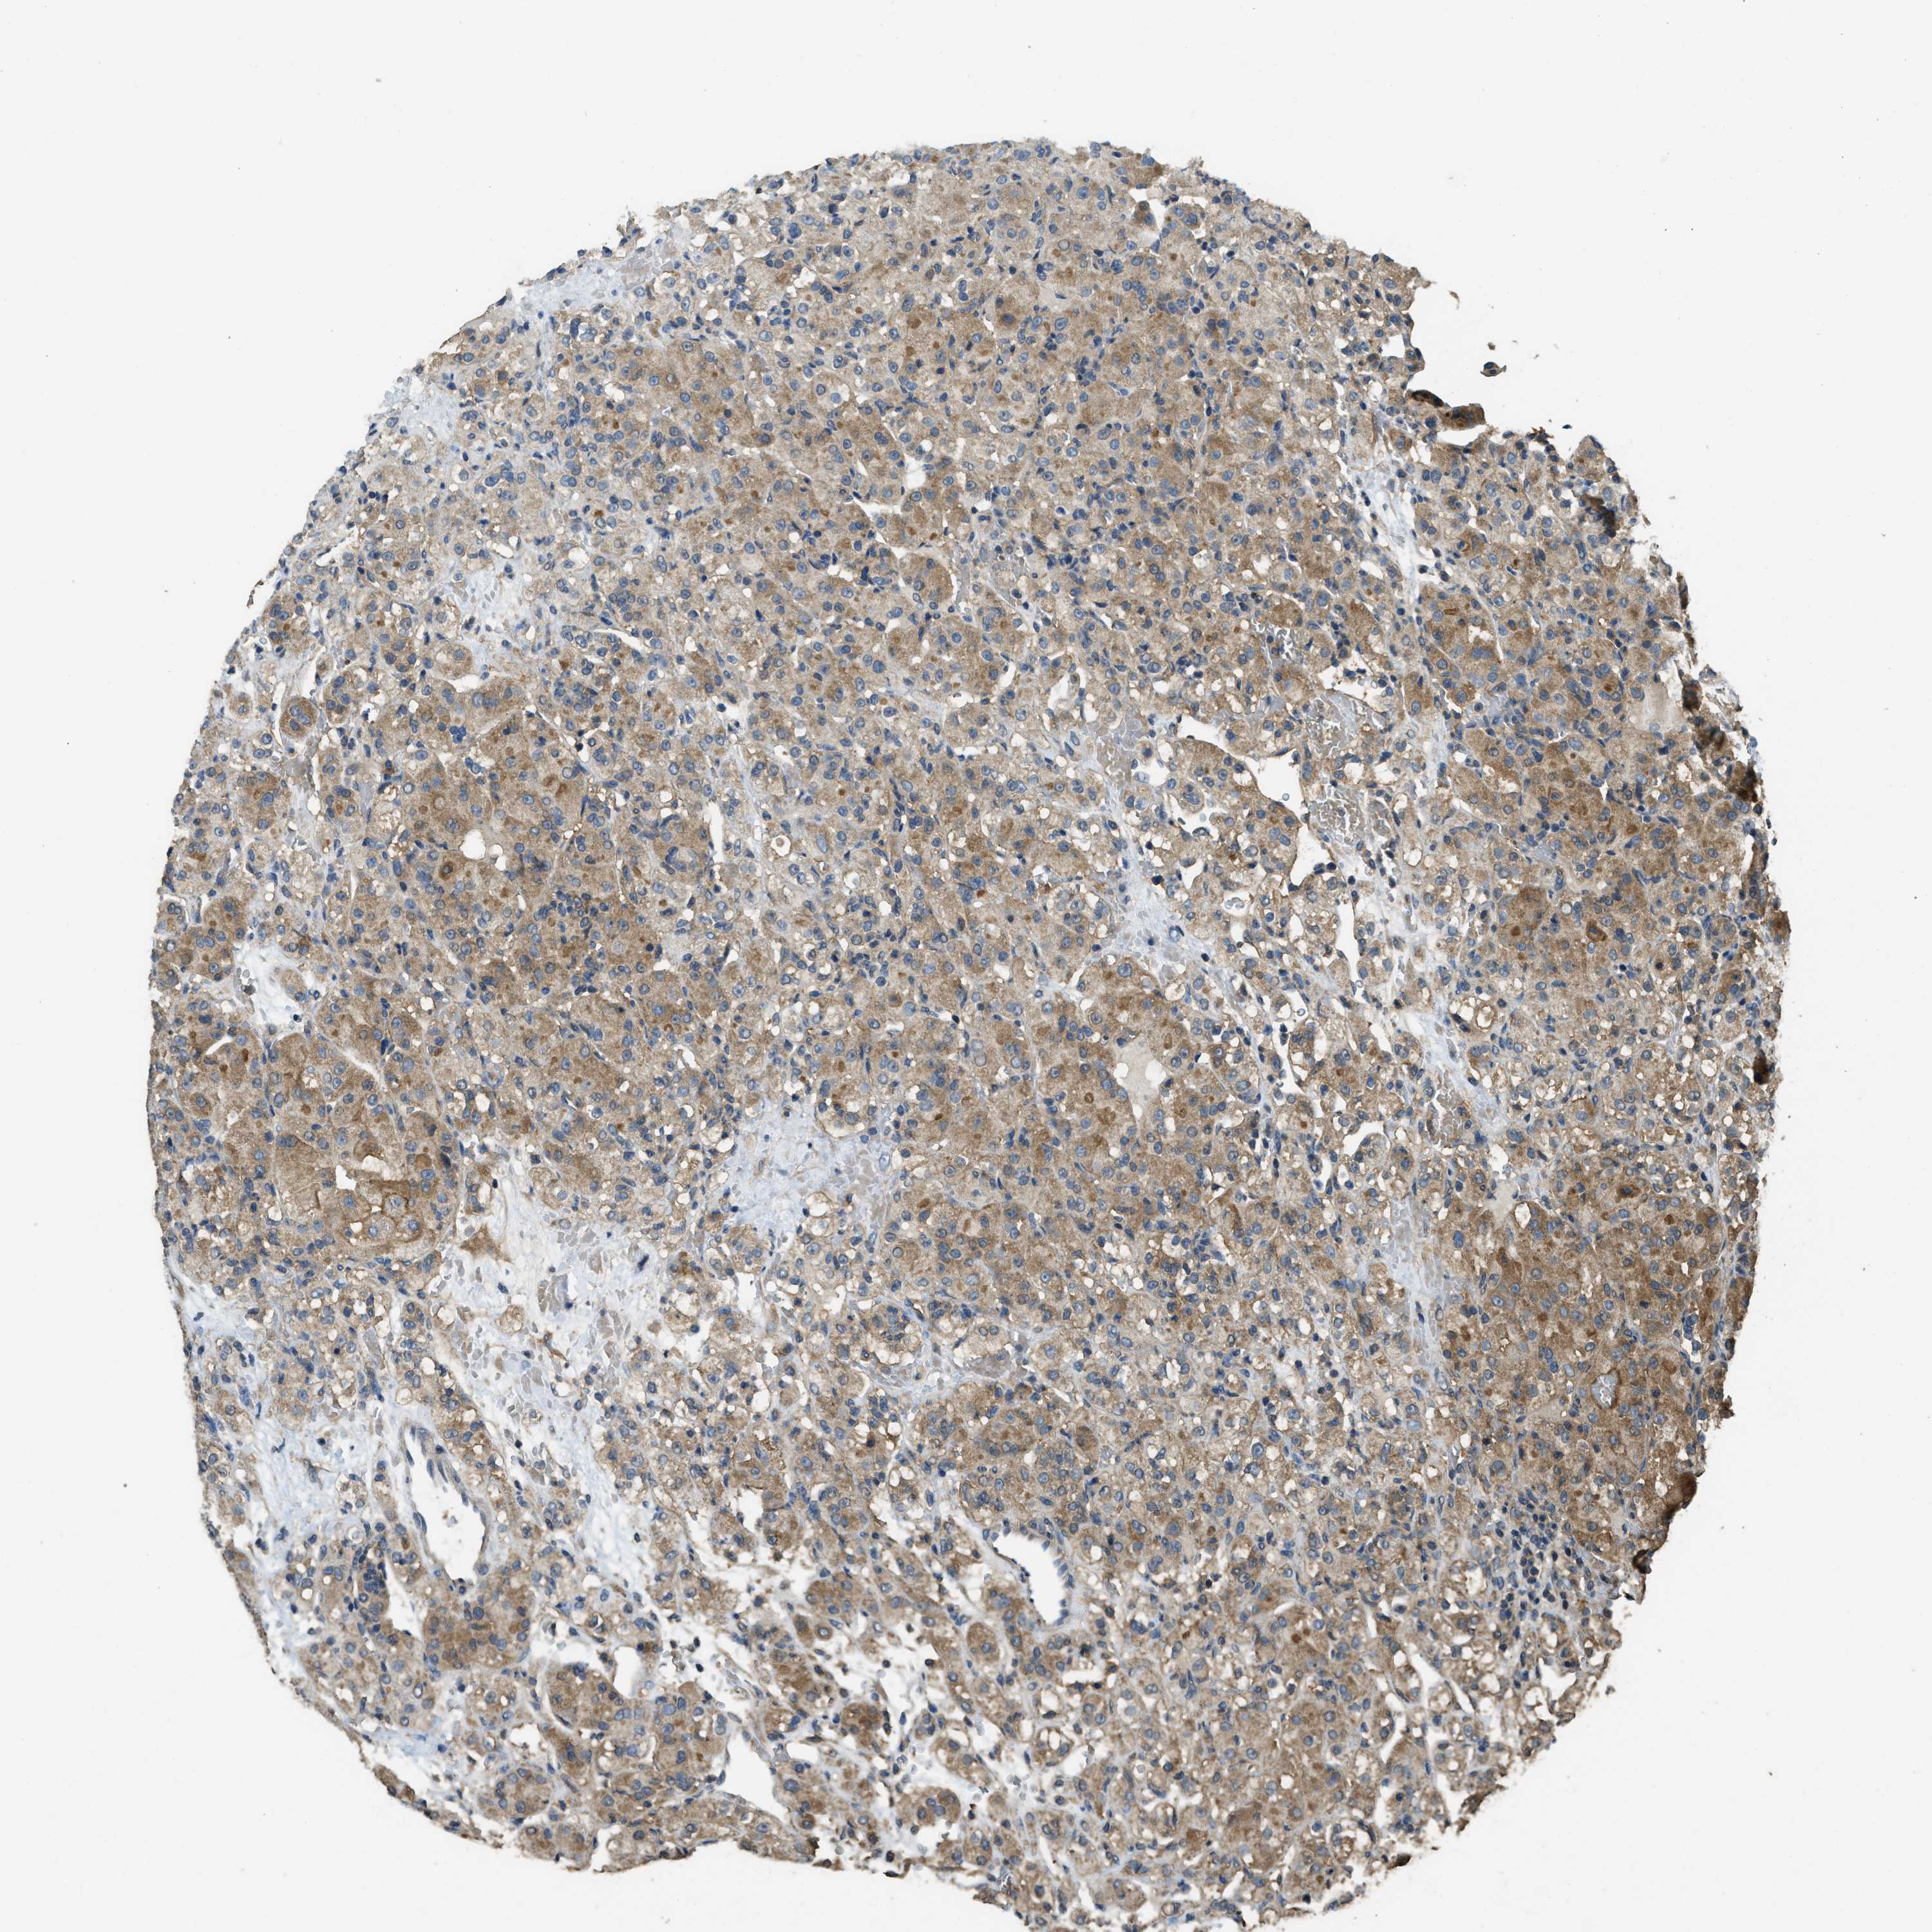

KIDNEY RENAL CLEAR CELL CARCINOMA (VALIDATION) - Interactive survival scatter ploti

The Survival Scatter plot shows the clinical status (i.e. dead or alive) for all individuals in the patient cohort, based on the same data that underlies the corresponding Kaplan-Meier plots. Patients that are alive at last time for follow-up are shown in blue and patients who have died during the study are shown in red.

The x-axis shows the expression levels (FPKM) of the investigated gene in the tumor tissue at the time of diagnosis. The y-axis shows the follow-up time after diagnosis (years). Both axes are complimented with kernel density curves demonstrating the data density over the axes. The top density plot shows the expression levels (FPKM) distribution among dead (red) and alive patients (blue). The right density plot shows the data density of the survived years of dead patients with high and low expression levels respectively, stratified using the cutoff indicated by the vertical dashed line through the Survival Scatter plot. This cutoff is automatically defined based on the FPKM cutoff that minimizes the p-score. The cutoff can be changed by dragging the vertical line or by entering a cutoff value in the square labeled "Current cut-off".

Under the Survival Scatter plot the p-score landscape (black curve; left axis) is shown together with dead median separation (red curve; right axis). Dead median separation is the difference in median mRNA expression between patients who have died with high and low expression, respectively. It is calculated as follows: median FPKM expression of dead patients with high expression - median FPKM expression of dead patients with low expression. This is intended to aid the user in visually exploring custom cutoffs and the associated p-scores and dead median separation.

Individual patient data is displayed and can be filtered by clicking on one or more of the category buttons on the top of the page. Categories describing expression level and patient information include: high, low, alive, dead, female, male and tumor stages. The scale of the x-axis can be toggled between linear and log-scale by clicking on the "x log" button. Mouse-over function shows TCGA ID, patient information and mRNA expression (FPKM) for each patient.

& Survival analysisi

Kaplan-Meier plots summarize results from analysis of correlation between mRNA expression level and patient survival. Patients were divided based on level of expression into one of the two groups "low" (under cut off) or "high" (over cut off). X-axis shows time for survival (years) and y-axis shows the probability of survival, where 1.0 corresponds to 100 percent.

CD276 is not prognostic in Kidney Renal Clear Cell Carcinoma (validation)

Best expression cut offi

Based on the FPKM value of each gene, patients were classified into two groups and association between prognosis (survival) and gene expression (FPKM) was examined. The best expression cut-off refers the FPKM value that yields maximal difference with regard to survival between the two groups at the lowest log-rank P-value. Best expression cut-off was selected based on survival analysis .

When clicking on this number, the vertical dashed line indicating cut-off, the interactive survival plot, and the Kaplan-Meier curve will be adjusted to show results based on the best expression cut-off.

: 20.56

TCGA RNA samplesi

RNA-seq data is reported as average FPKM (number Fragments Per Kilobase of exon per Million reads), generated by the The Cancer Genome Atlas (TCGA) .

Normal distribution across the dataset is visualized with box plots, shown as median and 25th and 75th percentiles. Points are displayed as outliers if they are above or below 1.5 times the interquartile range. FPKM values of the individual samples are presented next to the box plot.

Average pTPM 32.6

Number of samples 100